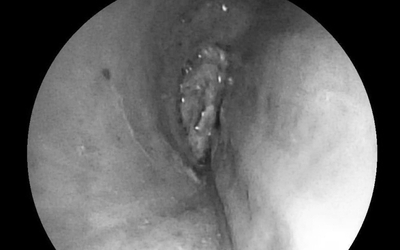

Bé trai 11 tuổi đau cổ, khó thở, bác sĩ gắp ra thứ "đáng sợ" bên trong

Ngày 1/10, Bệnh viện Nhi đồng Đồng Nai cho biết, vừa cấp cứu thành công trường hợp bệnh nhi Đ.Q.B. (11 tuổi, ngụ xã Phú Lâm, tỉnh Đồng Nai) hóc dị vật trong thực quản.